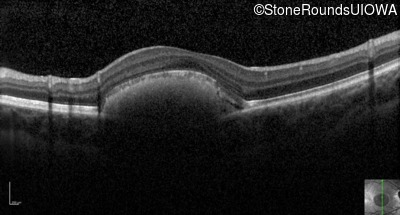

Optical Coherence Tomography - Left - 20/30 sc

Exemplar / OCT Stack